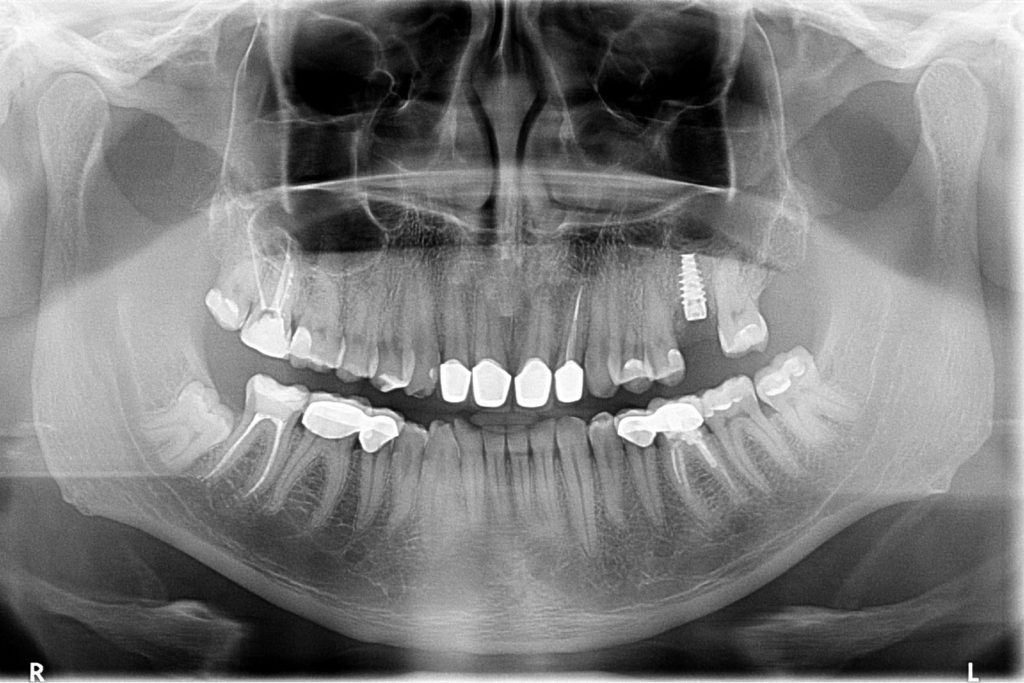

Przed podjęciem leczenia należy określić stopień zaniku kości szczęk oraz żuchwy. W tym celu przeprowadza się badanie kliniczne oraz odpowiednią diagnostykę obrazową pacjenta. Uwzględnia ona zdjęcie panoramiczne OPG jako podstawę dwuwymiarowego obrazowania podłoża kostnego oraz możliwe jest badanie tomograficzne CT lub bardziej precyzyjna tomografia stożkowa CBCT. Opcjonalnie wykorzystywana diagnostycznie tomografia pozwala na bardziej wnikliwą ocenę stopnia zaniku kości w trójwymiarowym, przestrzennym obrazie.